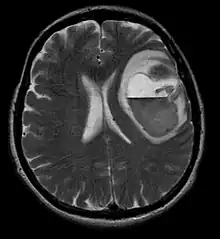

La tomodensitométrie (TDM) et L'imagerie par résonance magnétique (IRM) peuvent détecter efficacement une néoplasie dans le cerveau. L'IRM est plus sensible que la TDM pour identifier les lésions, mais présente des contre- indications pour les patients porteurs de stimulateurs cardiaques, de prothèses incompatibles, de clips métalliques et contre-indications. La TDM reste la méthode de choix pour détecter les calcifications au sein des lésions ou les érosions osseuses de la calotte ou de base du crâne. L'utilisation d' agents de contraste, iodés dans le cas du scanner et paramagnétiques (gadolinium) dans le cas de l'IRM, permet l'acquisition d'informations sur la vascularisation et l'intégrité de la barrière hémato-encéphalique, une meilleure définition de la tumeur tumorale par rapport à l' œdème environnant et à la génération d' hypothèses sur le degré de malignité. L'examen radiologique permet également d'évaluer les effets mécaniques et les modifications importantes des structures cérébrales résultant de la tumeur, telles que l' hydrocéphalie et les hernies, dont les effets peuvent être fatals. Enfin, en préparation à la chirurgie, ce diagnostic peut être utilisé pour déterminer la localisation de la lésion ou l'infiltration de la tumeur dans des zones vitales du cerveau. À cette fin, l'IRM est plus efficace que la tomodensitométrie car elle peut fournir des images en trois dimensions.

Les outils d'imagerie radiologique diagnostique mettent en évidence la modification du tissu néoplasique par rapport au parenchyme cérébral normal (par le biais de modifications de la densité tissulaire imagée électroniquement en TDM et de l'intensité du signal en IRM). Comme la plupart des tissus pathologiques, les tumeurs sont également reconnaissables par une accumulation accrue d'eau intracellulaire. Dans la tomodensitométrie, ils apparaissent hypodenses, c'est-à-dire de moindre densité que le parenchyme cérébral, dans la tomographie par résonance magnétique nucléaire avec relaxation spin-réseau hypointense et en relaxation spin-spin ainsi que l' hypersignal en pondération protonique (PD).

Sur-L'IRM montre une tumeur intracrânienne comme une lésion massive qui peut devenir plus luminescente après utilisation du produit de contraste. Cependant, il y a toujours une anomalie de signal dans -L'imagerie par résonance magnétique, qui indique la présence d'une néoplasie ou d'un œdème vasogénique. Habituellement, une luminescence accrue (amélioration du contraste) indique une tumeur d'un grade supérieur de malignité. Un anneau de contraste est caractéristique du glioblastome, avec la partie luminescente correspondant à la partie vitale de la tumeur maligne, et la plus foncée - zone hypointense correspondant à une nécrose tissulaire.